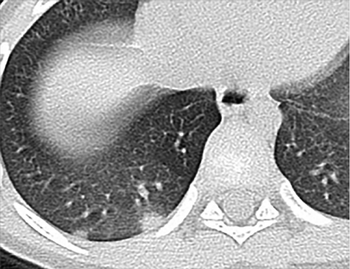

Percentage of lung opacities can be used to rate the severity of disease.

CT scan and video reveal peripheral, multilobar areas of ground-glass opacity.